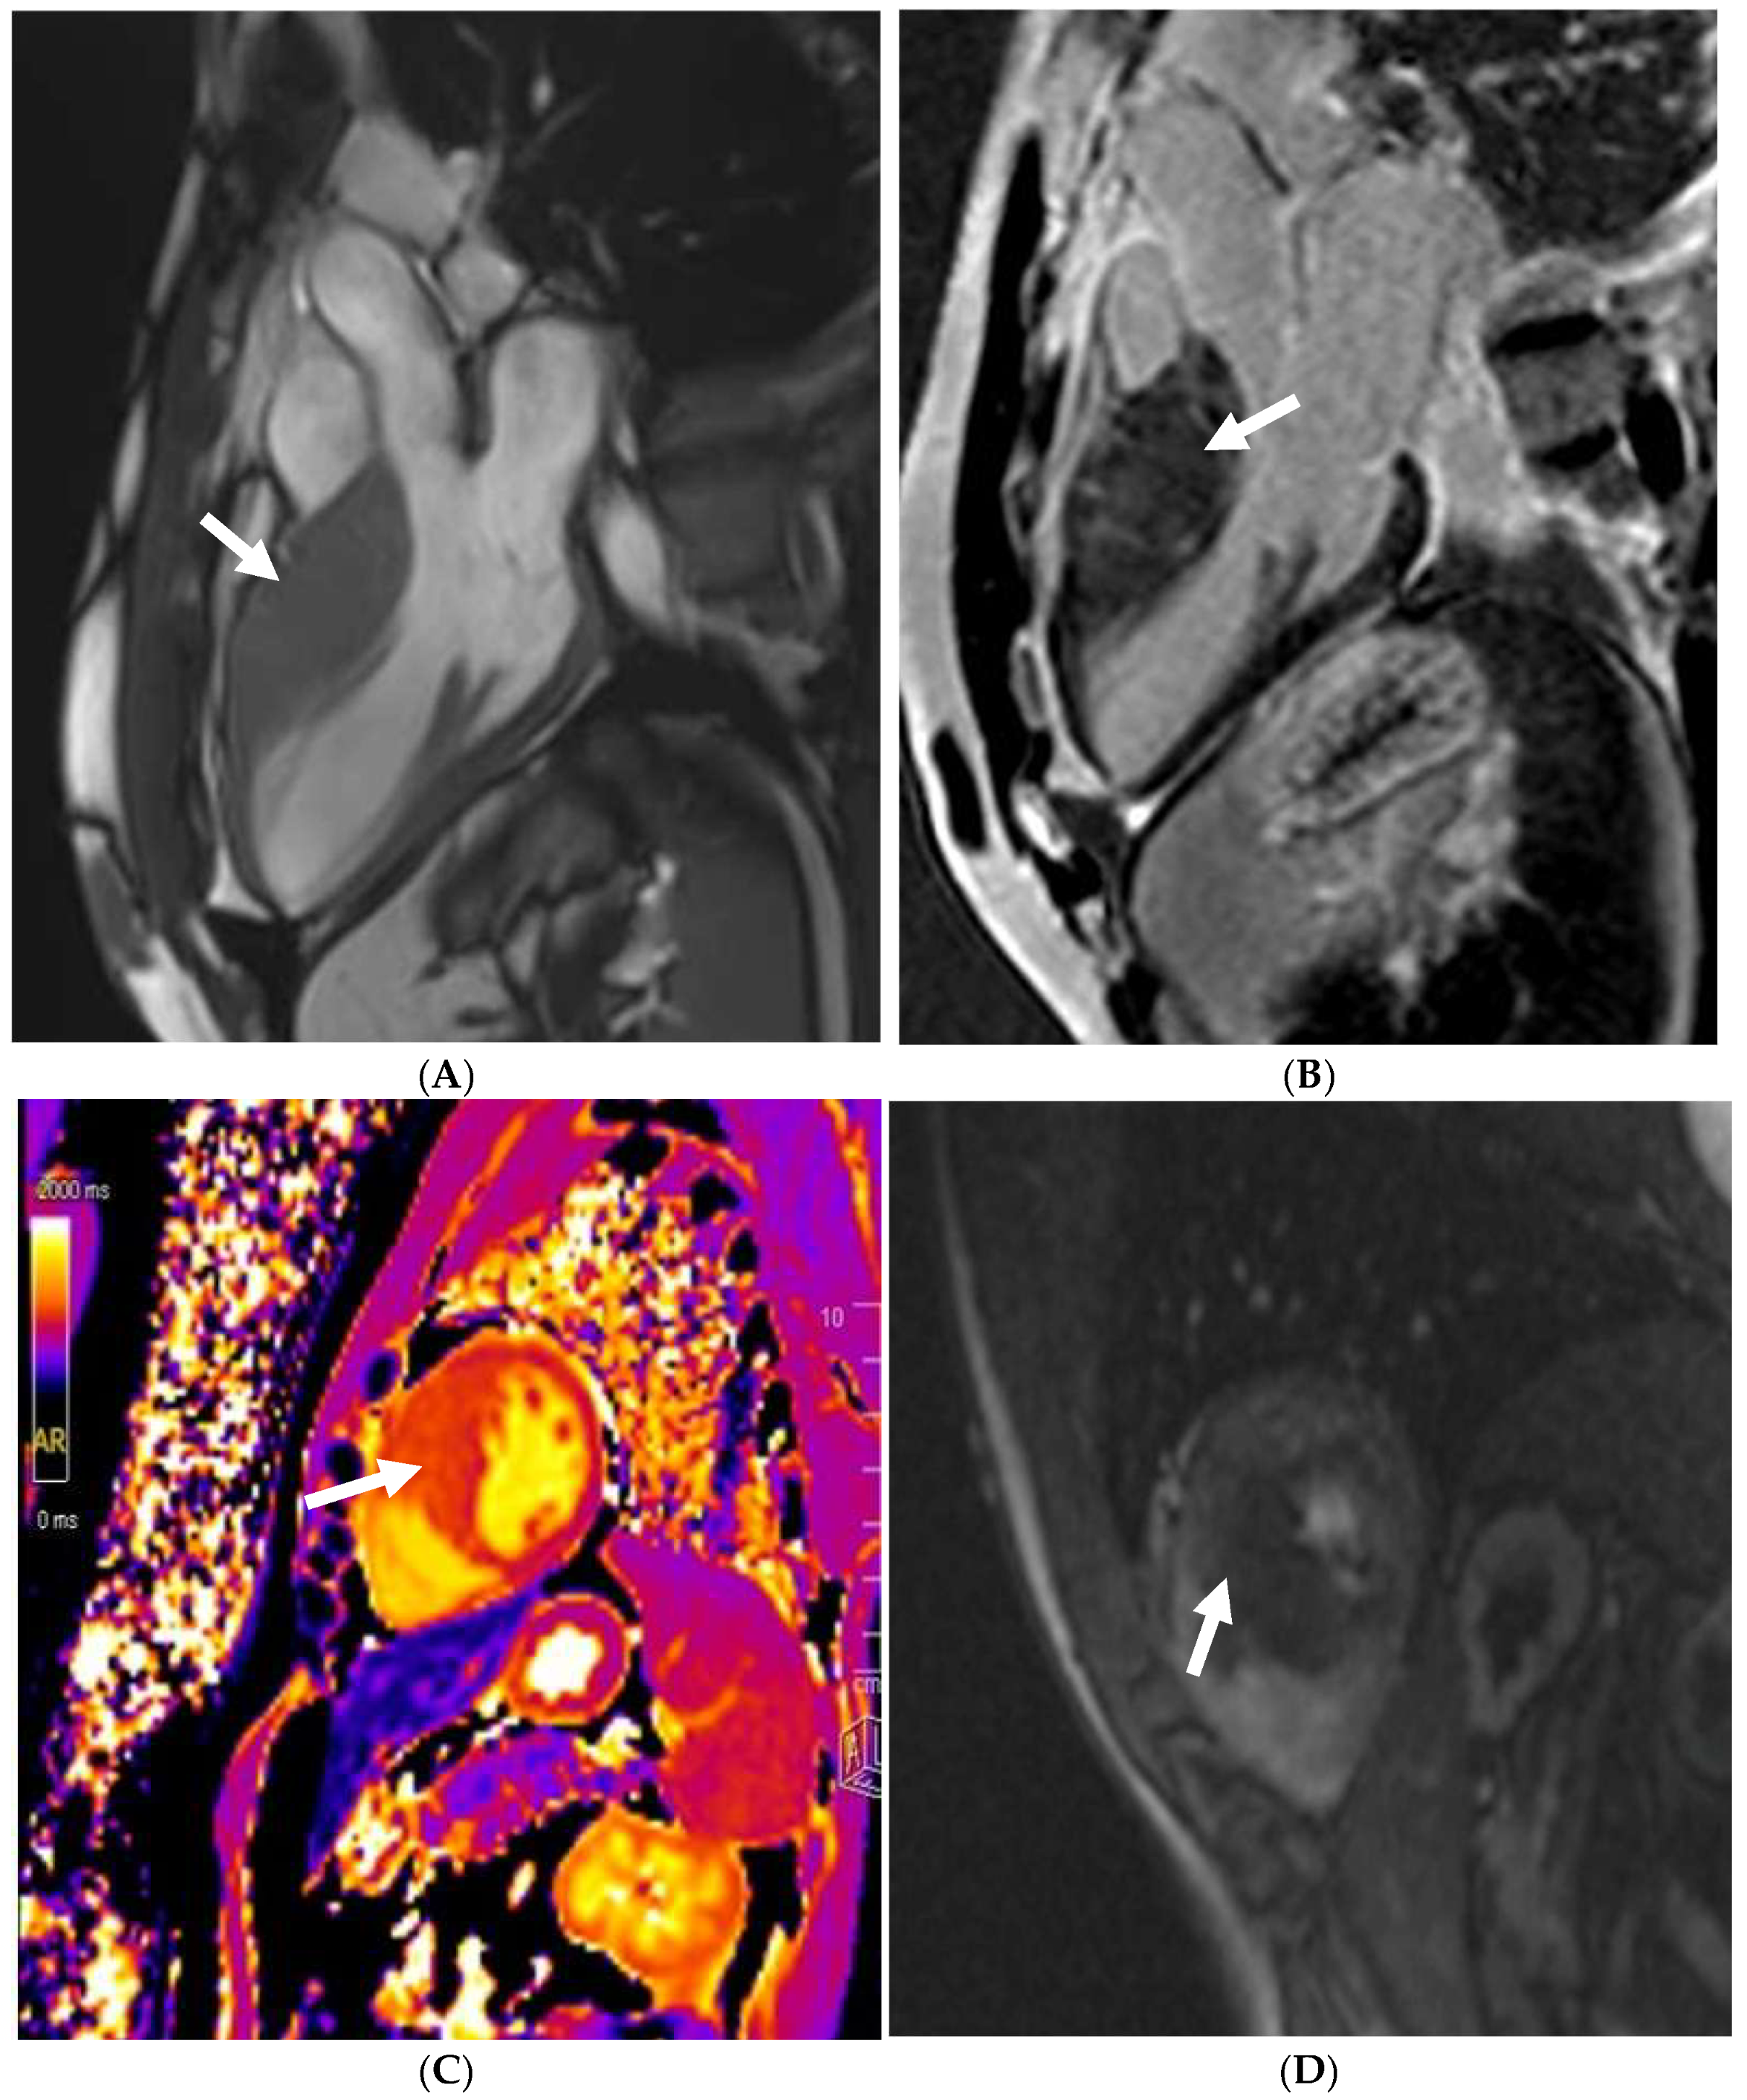

11. Left Ventricular Hypertrabeculation

19. Myocarditis

20. Pericarditis